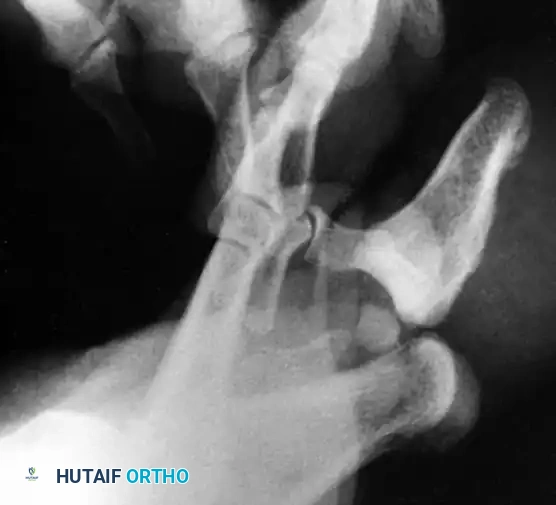

In a Type II dislocation, the distal phalanx lies completely dorsal to the proximal phalanx, locking the joint in severe hyperextension.

* Clinical Appearance: The deformity is obvious and rigid. The plantar skin is stretched taut or torn.

* Radiographic Appearance: The base of the distal phalanx overlaps the head of the proximal phalanx. If an IP sesamoid is present, it is often visible within the joint space, preventing reduction.